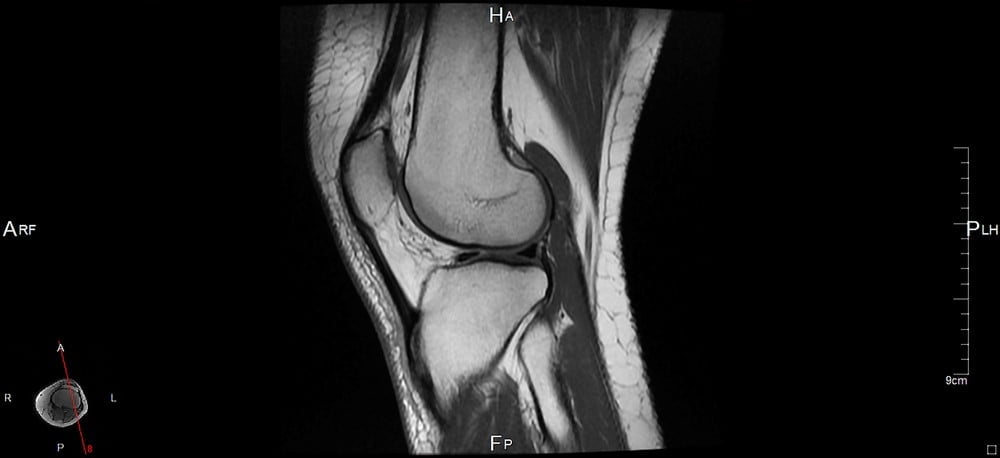

Szczególnie często wykonywany jest rezonans magnetyczny kolana, które jest jednym z największych, a zarazem najbardziej narażonych na urazy stawów.

Rezonans magnetyczny kolana do zobrazowania struktur kostnych i tkanek miękkich w obrębie stawu wykorzystuje unikalne właściwości pola magnetycznego, generowanego przez specjalistyczną aparaturę. Wzbudza ono atomy w naszych komórkach, a wysyłany przez nie sygnał odbierany jest przez specjalny detektor i za pomocą specjalnego oprogramowania przekształcany w precyzyjne obrazy. Są one bardzo dokładne i pozwalają na wykrycie nawet najmniejszych nieprawidłowości w obrębie stawów.

Co ważne, badanie jest całkowicie bezpieczne i nieinwazyjne, dzięki czemu nawet w krótkim czasie może być wykonywane wielokrotnie, bez negatywnego wpływu na zdrowie pacjenta. Po wykonaniu badania radiolog dokonuje oceny poszczególnych elementów, a także weryfikuje obecność krwawień i wysięków w obrębie jamy stawowej. W przypadku badania jakim jest rezonans magnetyczny kolana szczególnie istotna jest precyzyjna ocena więzadeł oraz zmian w chrząstkach stawowych.

Co może uwidocznić rezonans magnetyczny kolana? Przede wszystkim w wyniku badania uzyskujemy precyzyjny obraz struktury kluczowych więzadeł, tzn. więzadła krzyżowego przedniego oraz tylnego. Lekarz ma możliwość oceny nie tylko ich ciągłości, ale również położenia względem pozostałych elementów stawu. Następnie dokonywana jest ocena zbudowanych z tkanki chrzęstnej łąkotek, bocznej oraz przyśrodkowej. To właśnie nieprawidłowości w obrębie ich struktury zwykle odpowiadają za problemy z poruszaniem i bolesne dolegliwości.

Lekarz sprawdza również budowę kości oraz chrząstek stawowych. W stawie kolanowym często dochodzi w nich do uwodnienia, które powoduje stopniową destrukcję tkanek. Rezonans magnetyczny kolana odgrywa również istotną rolę w diagnostyce procesów nowotworowych. W badaniu można zobrazować zmiany nowotworowe zarówno w obrębie kości, jak i tkanek miękkich czy szpiku kostnego.